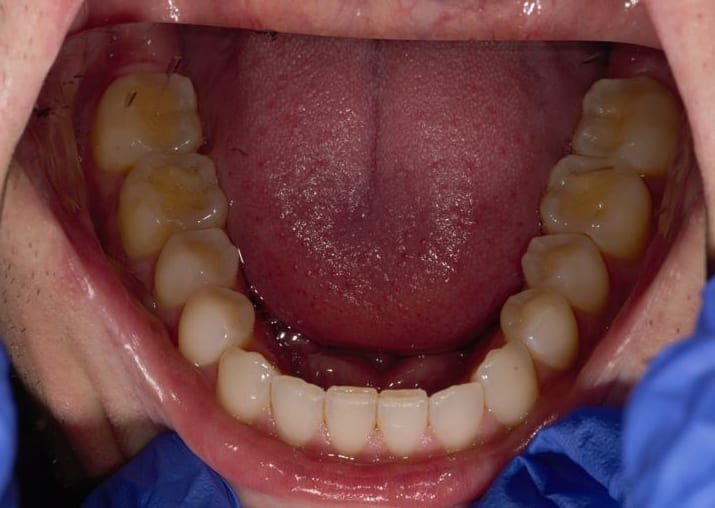

Que proposer à mon patient de 31 ans, pratique sportive régulière (juste de l'eau, rarement du sucre), non fumeur, avec une usure assez marquée des molaires (a priori je dirai des usures d'origine chimique associée à du bruxisme) dont je vous joins ici les photos.

Les molaires étaient sensibles il y a quelques mois à l'alimentation, mais depuis la fluoration et l'utilisation de dentifrice adapté (Mirasensitive HAP+), les sensibilités apparaissent uniquement lorsque j'utilise une sonde exploratrice sur la face occlusale.

Les usures évoluent sensiblement d'année en année (suivi photo).

Je vous joins les photos

J'ai modifié les photos, j'avais posté 2x la machoire supérieure, mais pas l'inférieure qui est plus usée, nott sur 36. J'en rajoute un peu en voila dautres.

Pour moi j'étais certain du diagno de RGO, vu les faces occlusales, et vu les faces incisales des 42 à 32.